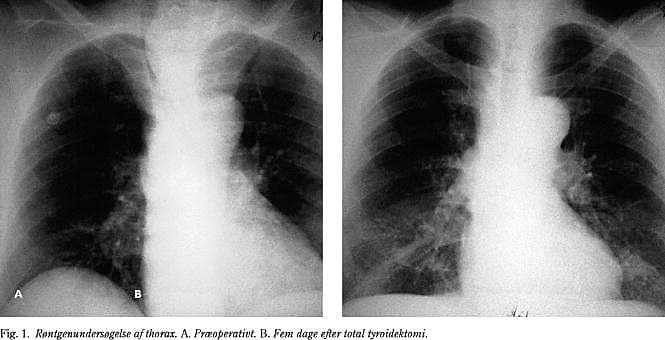

Røntgenundersøgelsen viste kompression af trachea i næsten alle tilfælde. Kun i to tilfælde med symptomer på øvre luftvejsobstruktion viste almindelig røntgenundersøgelse med forfra- og sideoptagelse ingen forsnævring. I de øvrige 31 tilfælde var der kompression af tracheas lumen i varierende grad, ofte med en betydelig dislokation. Den postoperative røntgenundersøgelse viste i alle tilfælde en betydelig bedring og en normalisering af tracheas lumen. Denne effekt indtraf hurtigt, undertiden i løbet af få dage, og subjektivt bedredes respirationen meget hurtigt, ofte i løbet af få timer (Fig. 1 og Fig. 2).